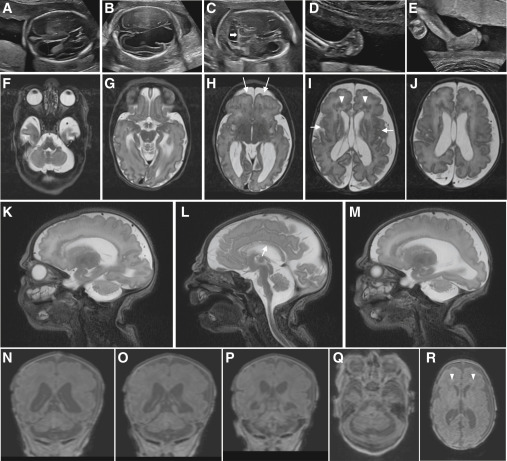

Fig. 2 Clinical imaging of the family B and family E probands who harbor bi-allelic variants in SNAPIN (A–E) Prenatal ultrasound imaging of the family B-II:3 fetus showing progression of ventriculomegaly at (A) 19 to (B) 21 weeks of gestation, with disruption of ventral parenchyma at 21 weeks; (C) cerebellar hypoplasia at 21 weeks of gestation (white horizontal arrow); and (D and E) progression of clubfeet at (D) 19 to (E) 21 weeks. (F–R) Brain MRI of the family E-II:3 proband, born at 38 weeks of gestation, at 3 days of age showing a complex brain malformation including microcephaly with simplified gyral pattern (arrows, H), polymicrogyria (arrows, I) (G–R), thin corpus callosum (arrow, L), bilateral enlargement of lateral ventricles (H–J, N, and O), prominent periventricular white matter lesions suggestive of mixed subcortical heterotopias (arrow heads, I and R), and pronounced pontocerebellar hypoplasia (F, L, and Q). (F–J) T2-weighted axial images, (Q and R) T1-weighted axial images, (K–M) T2-weighted sagittal images, and (N–P) T1-weighted coronal images.